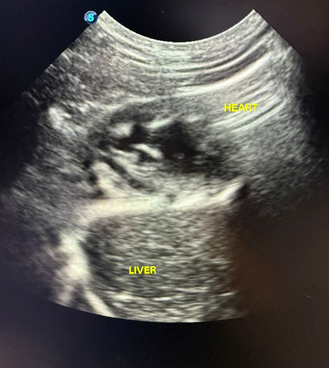

X光檢查顯示,原本應位於腹腔內、緊貼橫隔膜下方的肝臟,異常出現在胸腔範圍內。超聲波檢查亦進一步顯示,肝臟位置接近心臟,屬非常異常的表現。

圖三| 超聲波檢查顯示肝臟位置接近心臟,屬極不正常表現,提示橫隔膜破損及腹腔器官胸腔移位。